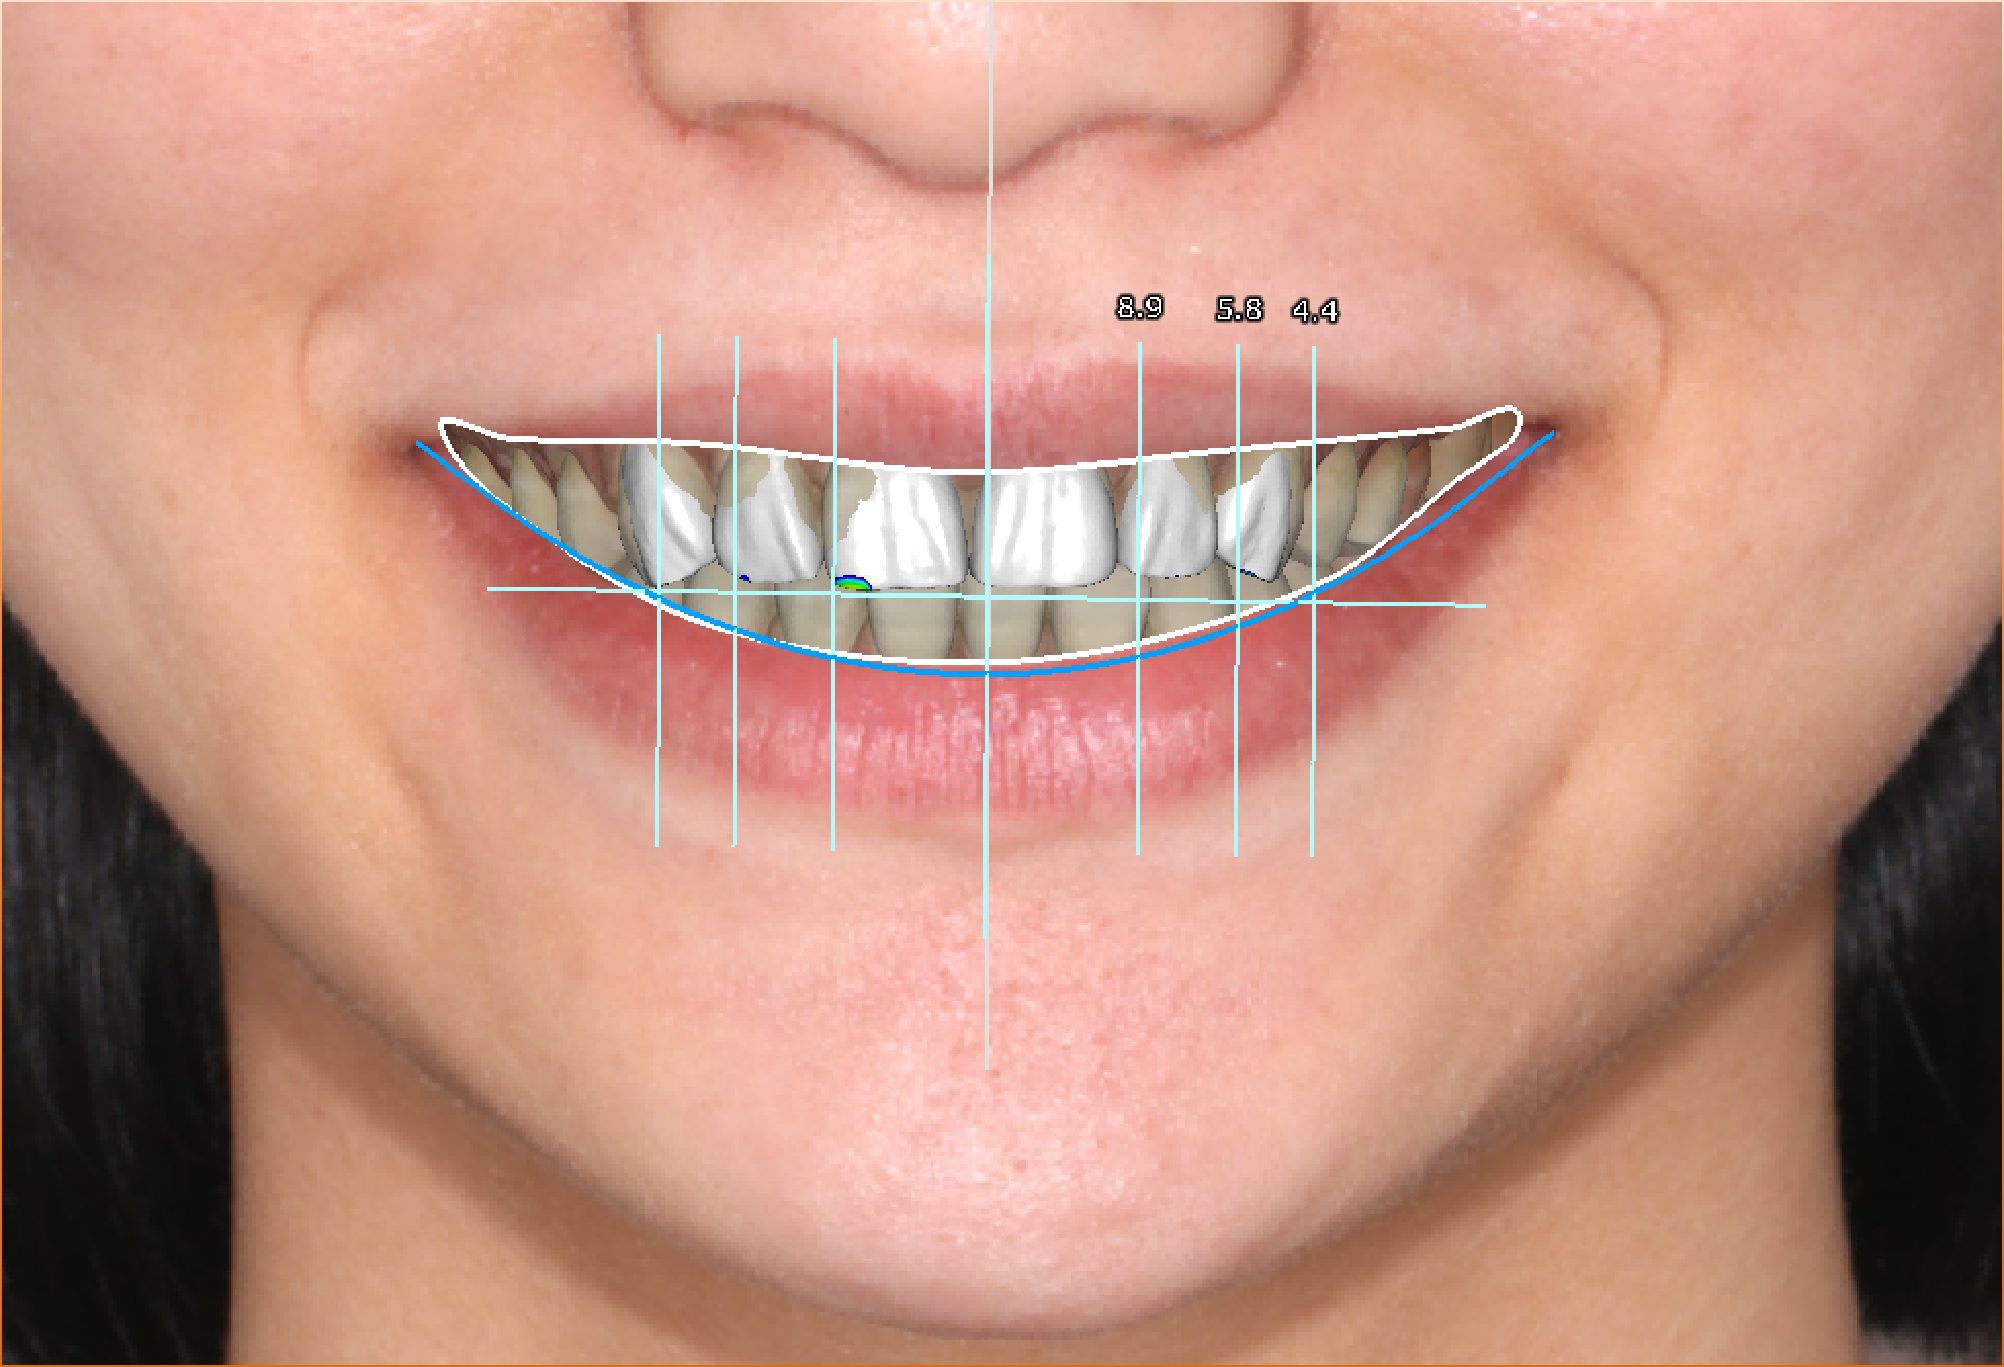

真实案例

TRUE CASE